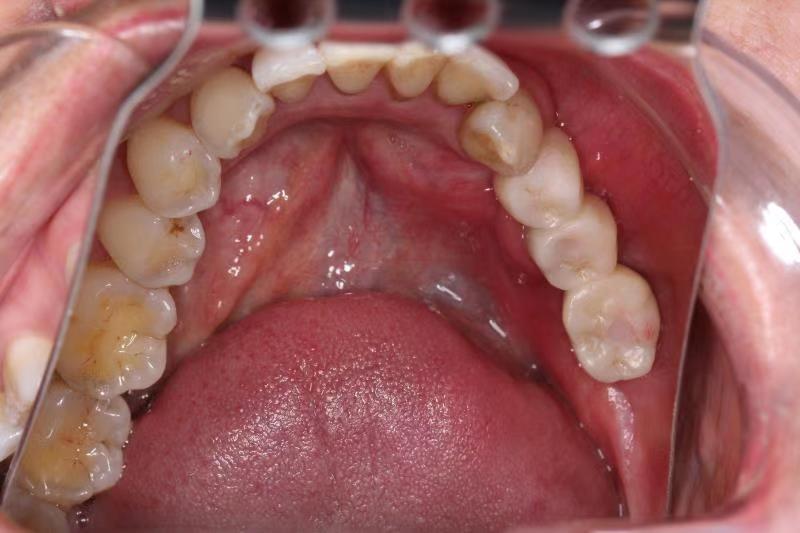

二、针对肿瘤、创伤治疗术后的复杂颌骨、牙列以及软组织缺损,采用种植技术联合骨移植进行功能性重建,尽最大程度恢复患者的咀嚼、发音以及吞咽等口腔功能,提高患者生存质量。(图为下颌骨区段缺损游离腓骨肌皮瓣移植术后行牵引成骨,二期种植行种植修复。